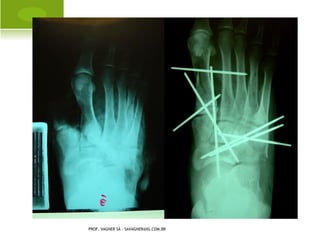

P É TORTO C ONGÊNITO

PROF. VAGNER SÁ - SAVAGNER@IG.COM.BR

C IRURGIA